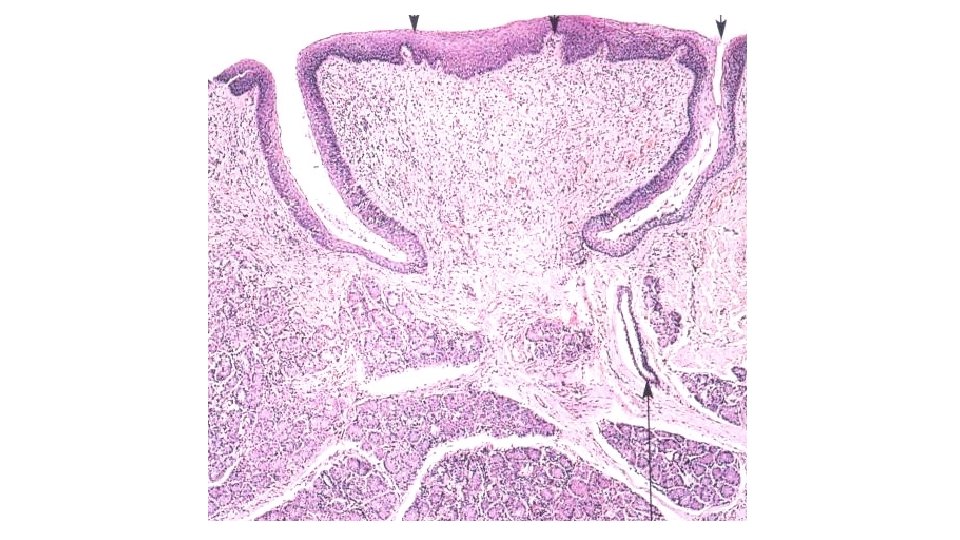

PAPILLA FILIFORMIS PAPILLA FUNGIFORMIS PAPILLA FOLIATA PAPILLA VALLATA

Papilla fungiformis Papillae filiformes Papilla fungiformis